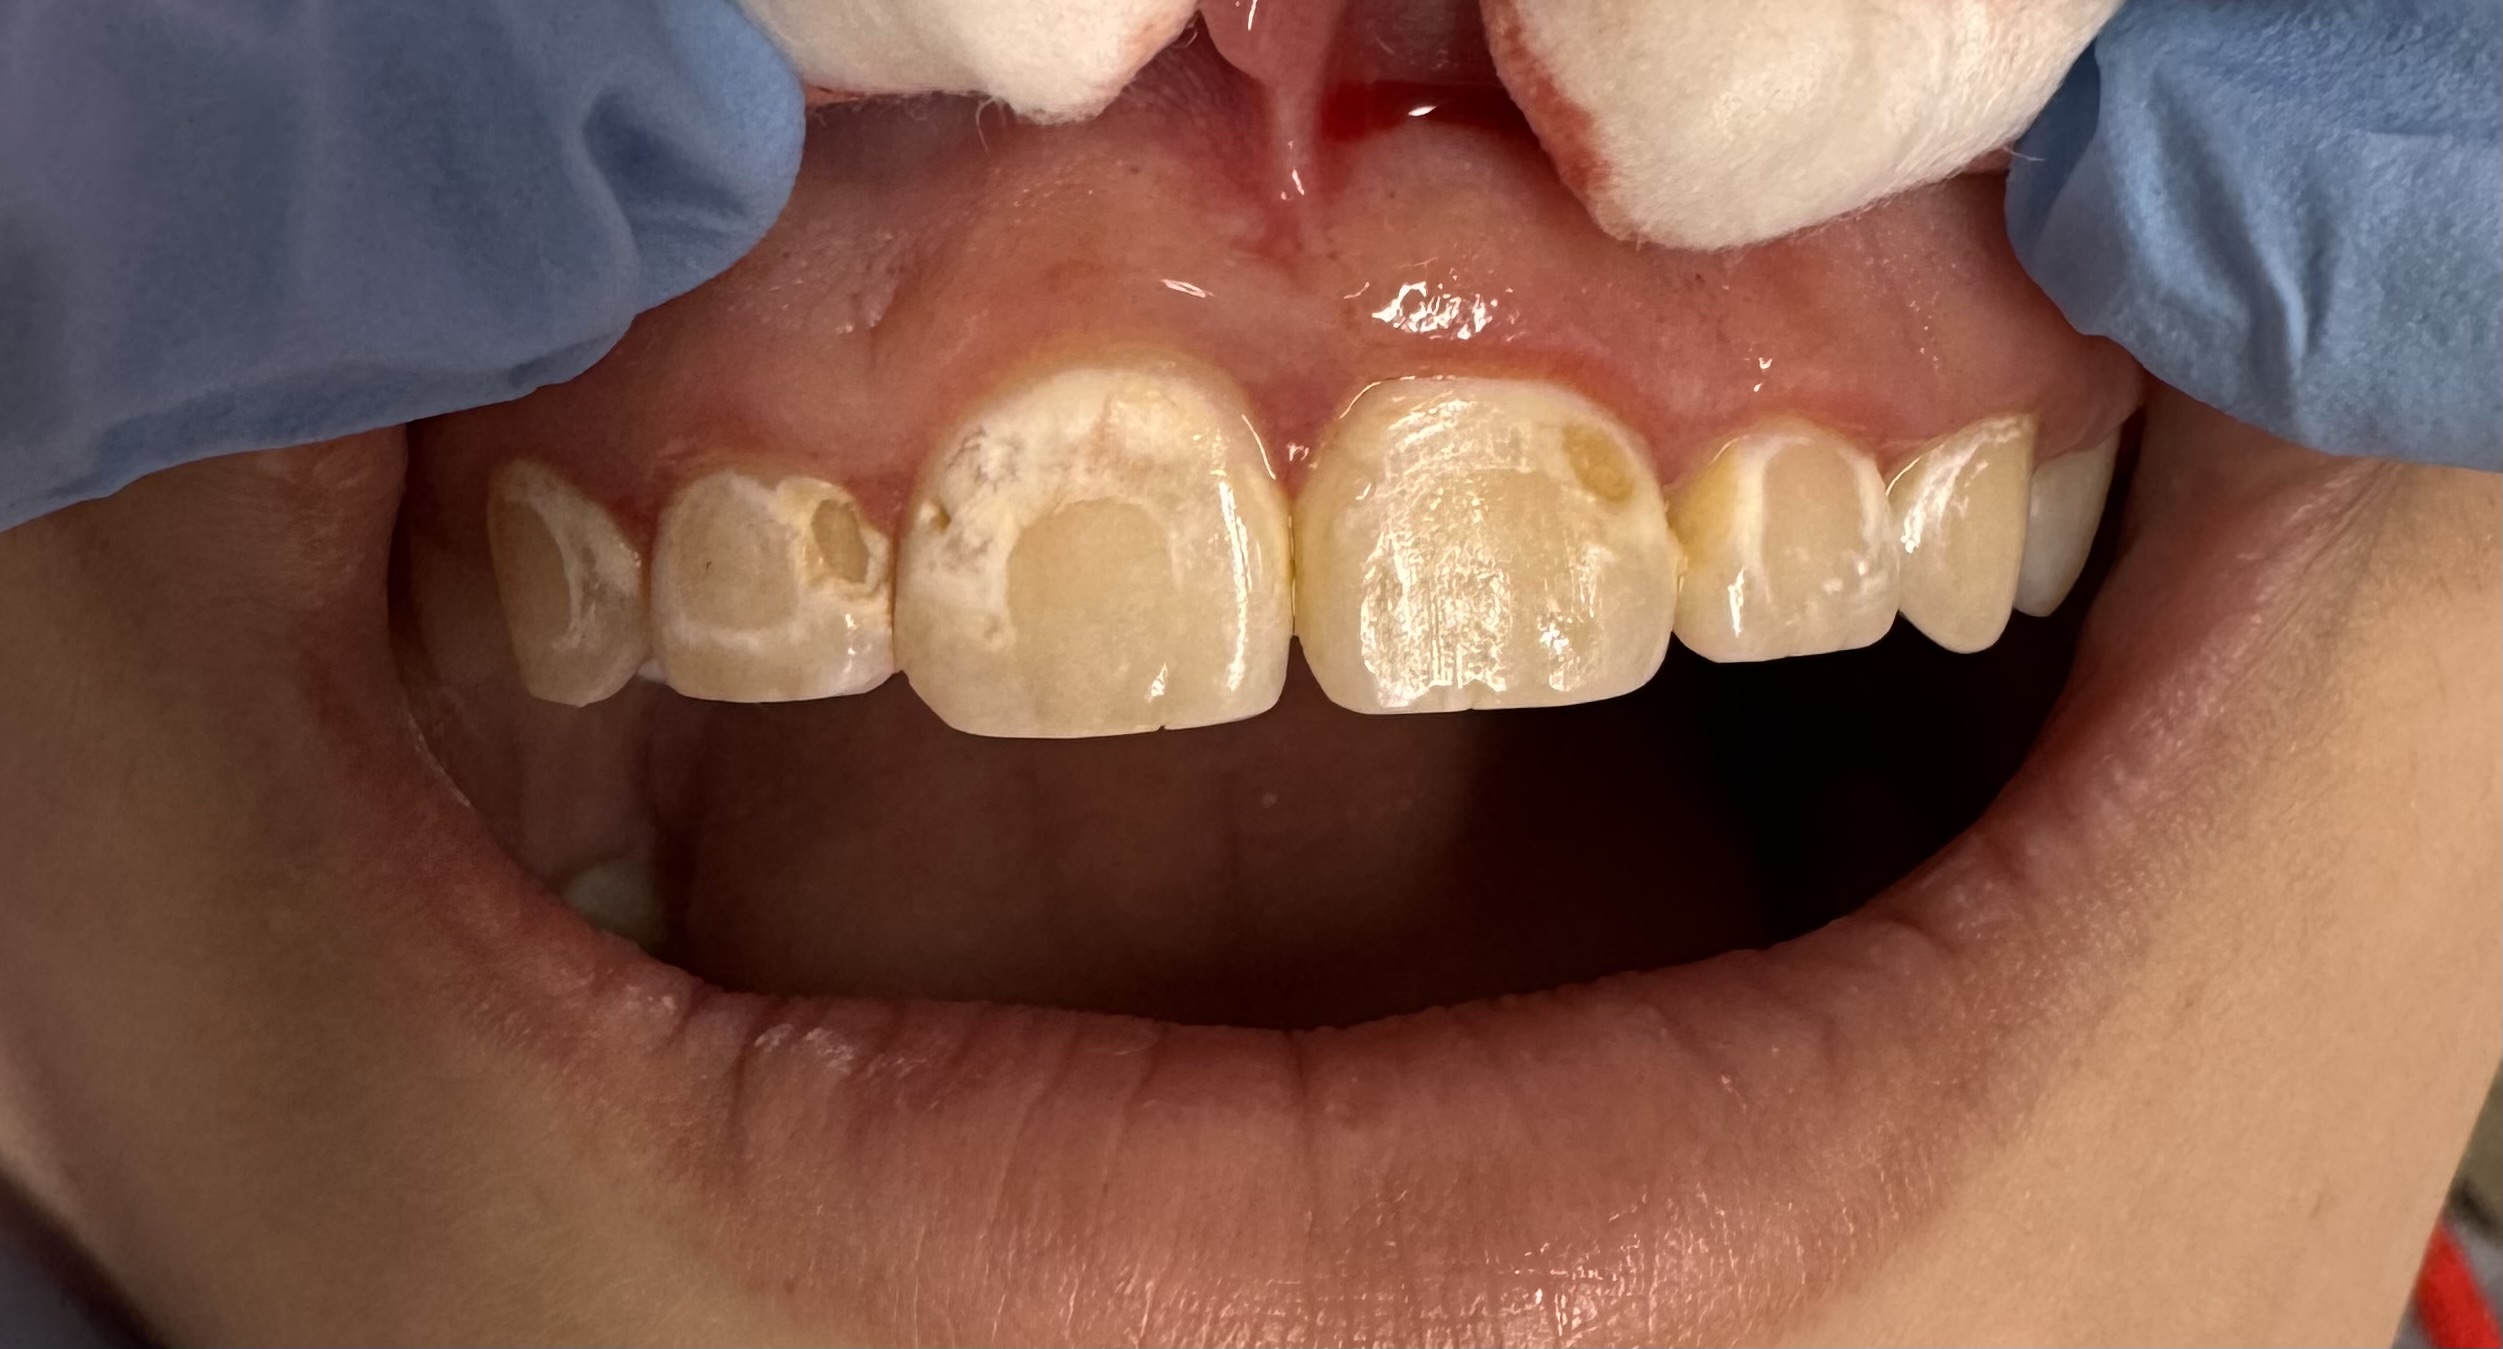

A teenage patient came to see Dr. Pashmini soon after she had her braces removed, and cavities were present on all her front teeth, where the brackets used to be.

This patient presented with a significant and deeply concerning issue: issues were caused by braces and multiple cavities caused by not brushing/flossing thoroughly during the treatment. This wasn’t merely a cosmetic concern; the patient had been living with this condition for an extended period, leading to considerable discomfort, multiple cavities and a decline in their overall quality of life. The impact extended beyond physical symptoms, affecting their confidence and daily interactions.

Dr. Pashmini and the dedicated team at Serenity Dental Spa devised a comprehensive and personalized treatment strategy to address the patient’s unique needs. The carefully planned approach involved composite fillings were done on all teeth on the same day. This meticulous process was designed not only to alleviate the immediate symptoms but also to ensure long-term oral health and aesthetic improvement, restoring both function and beauty to the patient’s smile.